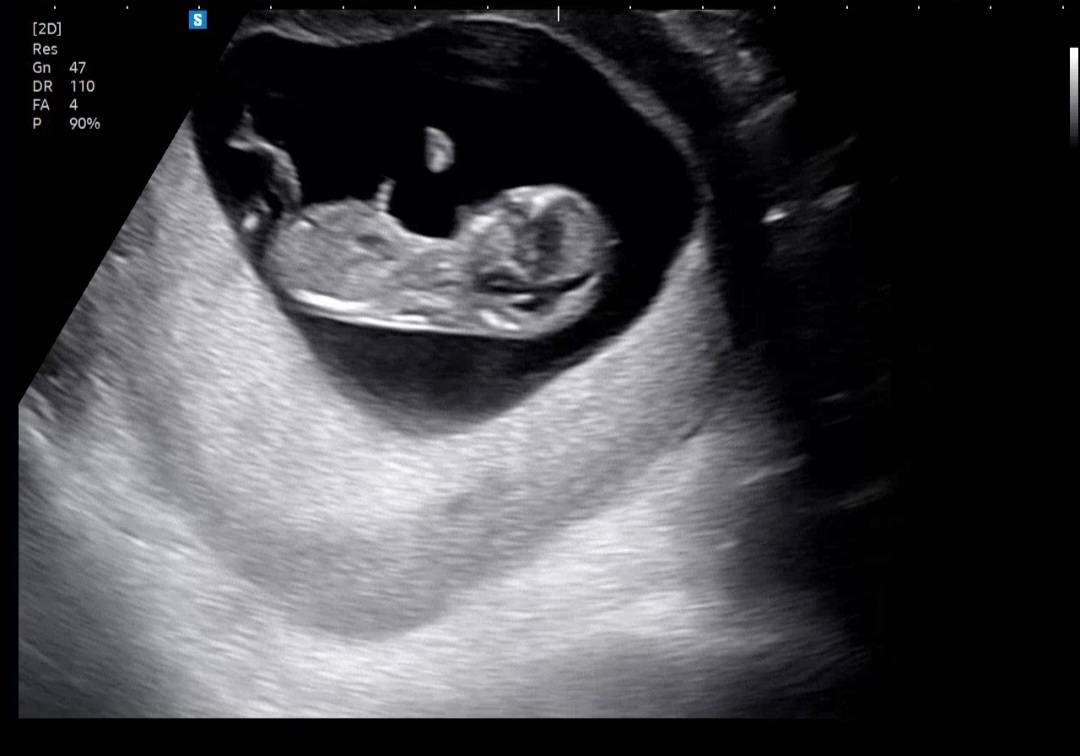

11주 6일 일란성쌍둥이 각도법 궁금해요! 많이 많이 참견해주세요~

현재는 12주차이고 대학병원에 정밀초음파하러 갔는데 대학병원이라서 그런지 입체초음파만 주시고 일반초음파 사진은 안주셨어요. 그리고 제 담당선생님은 성별을 아주아주 늦게 알려주실 것 같더라구요 ㅜㅜ 12주차때는 확실하지도 않고 성별보다는 건강하게 태어나는게 중요하지 않냐며..(그야 당연하고.. 저 역시 그렇게까지 안 궁금하다고 생각했었는데 아니였나봐요.. 안 가르쳐주시니까 갑자기 너무 너무 궁금해요 ㅎㅎ) 11주 6일차 서브병원에서 찍은 사진으로나마 대체해봅니다. 일란성쌍둥이이고 사진은 2명 모두입니다! 하나만 첨부가 되어서 다른 한명은 댓글로 올려놓을게요~ 많이 많이 참견해주세요ㅡ!

또 다른 아이의 사진이에요~!!